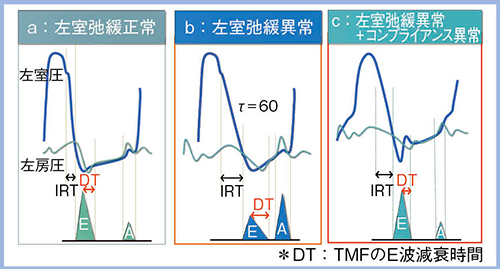

左室拡張機能を考える上で重要な左室圧曲線と左房圧曲線の関係(図2)を見ると,左室弛緩が正常な場合は左室圧曲線の下行脚がスムーズに低下して等容弛緩時間(IRT)が短くなり,E波もしっかりと保たれる(a)。一方,左室弛緩異常が進むと左室圧曲線の下行脚がなだらかとなってTauが延長し,IRTが延びてE波が減高するとともに,心房収縮によって左室の充満が保持されるため左房収縮期波(A波)が増高する(図2 b)。さらに,コンプライアンス異常が加わると,左房圧が上昇してIRTがやや短くなるためE波が急峻となり,またすぐに左室圧が上昇するためA波が減高する(図2 c)。この時,TMFのE波とe’に注目して左室弛緩を評価していくが,それを非常に簡便に行えるようにした技術がDual Gate Dopplerである2)。

図2 左室圧曲線と左房圧曲線の関係